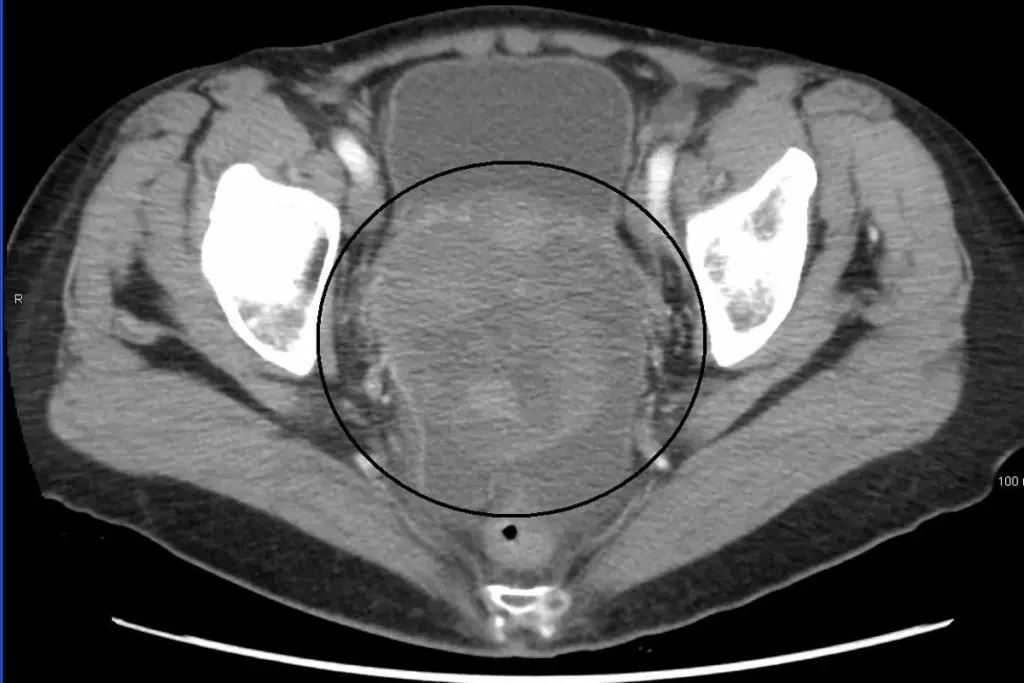

Transvaginal Ultrasound Applications

Transvaginal ultrasound is another tool used to screen for ovarian cancer. It can spot abnormalities in the ovaries. But, it’s hard to tell if these are cancerous or not. Scientists are trying to make this tool more accurate.